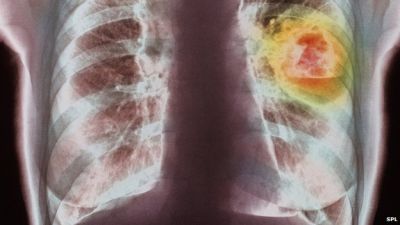

Lung cancer, which is mainly caused by smoking, was the most common cancer globally, with 1.8 million cases - about 13% of the total.